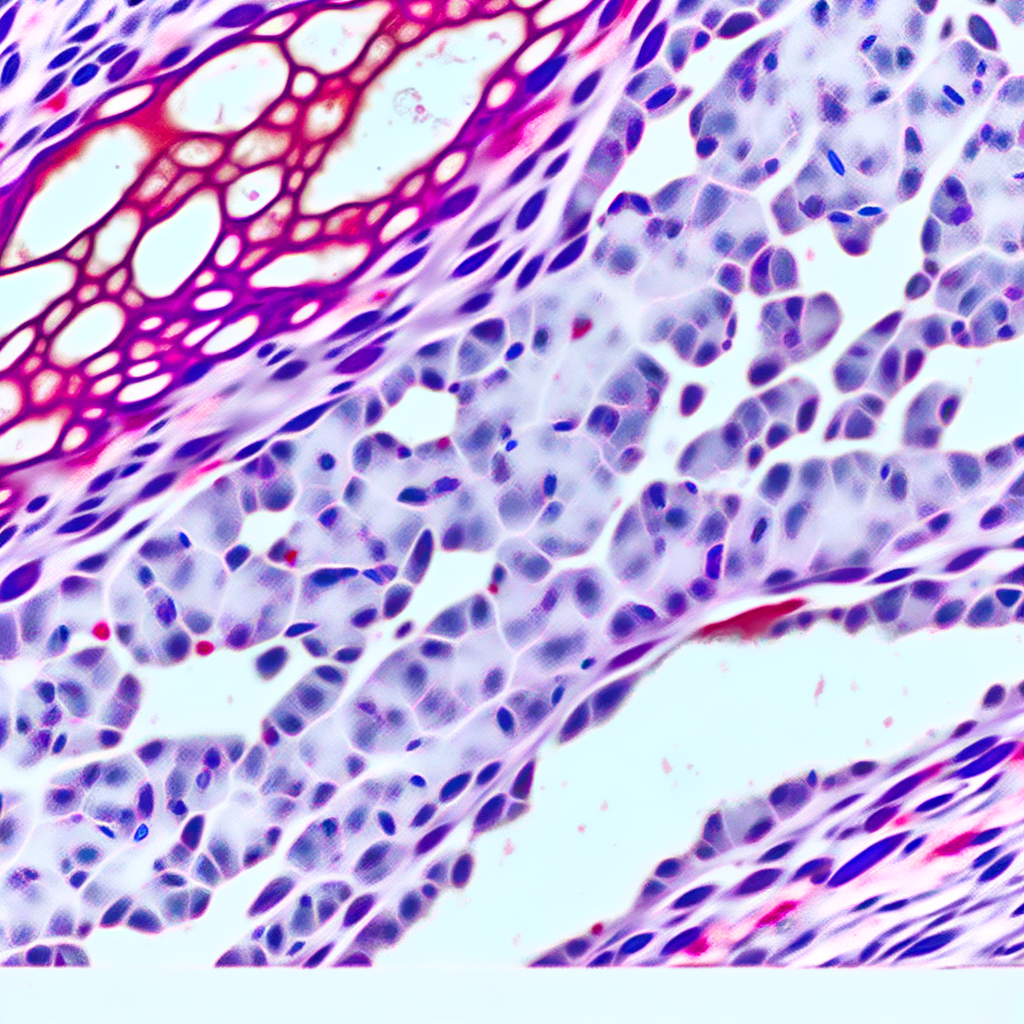

Researchers at the National Institutes of Health (NIH) have made a significant breakthrough in breast cancer research. Their discovery of a tissue biomarker offers new hope for identifying individuals at higher risk of developing aggressive breast cancer and experiencing worse outcomes. This advancement could pave the way for more personalized and effective treatment strategies.

Understanding who is more likely to develop aggressive forms of breast cancer is crucial for early intervention and improved survival rates. The NIH team’s findings highlight the potential of this biomarker as a predictive tool, which could transform current diagnostic and therapeutic approaches. Read the article on the NIH website for a detailed overview of the study and its implications.